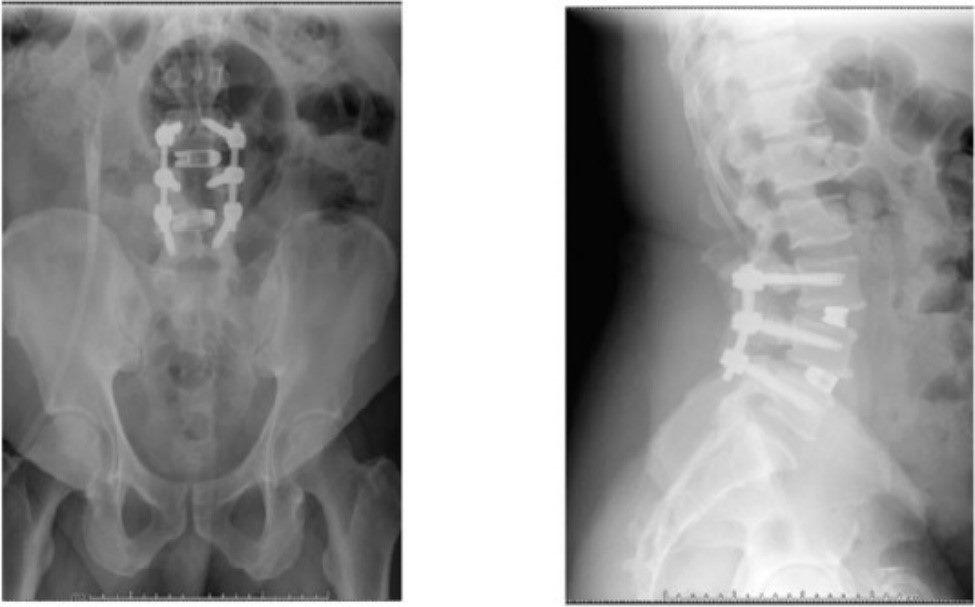

臺北市立聯合醫院中興院區骨科主治醫師劉彥麟曾經遇過一位眉頭深鎖的病患,一跛一跛的走進診間,苦惱的說:「醫生,我沒辦法好好走路已經有一段時間了,雙腳站一下就很痠痛麻木不舒服,諮詢過很多醫院都建議開刀,不知道你的意見如何?」從當時病患的X光影像可以看出來,第三腰椎至第五腰椎滑脫,且外院的核磁共振影像也顯示有嚴重的椎管狹窄,病人表示已接受過藥物保守治療以及復健,但效果不明顯。在與病人多次溝通並詳細解釋開刀風險及日後恢復情況後,病患決定開刀治療,手術解決了病患雙腳麻木痠痛的問題,也改善行走情況,回家上下樓梯已經不再是很痛苦的事情,甚至站立超過三十分鐘以上都沒有問題,生活上得到很大改善,最重要是終於看到他的笑容。

第三至第五腰椎滑脫 (圖片來源為國際外科雜誌) |

※圖片來源:Jonathan McKeeman, Emily Zielinski, Flynn A. Rowan, L3-L4/L4-L5 Type II-A spondylolisthesis: A case report, International Journal of Surgery Case Reports, Volume 124, 2024,